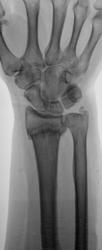

Травма. направлен на рентгенографию лучезапястного сустава

Поперечный перелом луча в типичном месте с разгибательной (сколько-то градусов) деформацией оси, боковым смещением на ширину кортикала, захождением ≈ 4 мм, перелом ШОЛК с/с.

Для оценки кистовидно измененной полулунной кости и исключения "дыр" в основании 4 пястной кости... укладку и центровку на кисть - и картина, возможно, поменяется)).

Где тут намечающаяся костная мозоль, где закругленные края линии перелома? Не увидела. На увеличении снимка - акварель)):